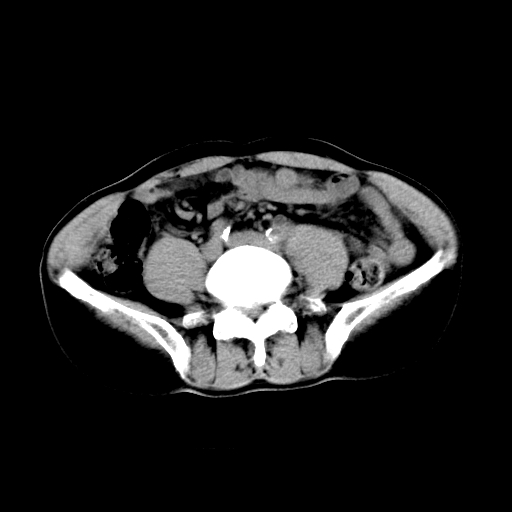

男,47岁,左输尿管结石碎石治疗后10余日。彩超示:左输尿管下段狭窄、输尿管积水。请各位讨论一下左输尿管下段结石还是静脉石?

象是第二狭窄处结石伴以上输尿管、肾盂轻度积水。

输尿管结石伴以上输尿管、肾盂轻度积水。

两侧髂总动脉壁斑状及点状钙化.左侧输尿管行经与左髂总动脉相交后见高密度影,且下段输尿管管腔未见扩张,应该要考虑结石伴以上输尿管及肾盂积水.但右侧结节状高密度影,也应该是结石吧!那以上输尿管未见扩张呢!因此静脉结石可能性也较大.请问楼主碎石前左侧输尿管结石位置.

虽左侧有轻度肾盂积水但不支持结石。1结石边周应该有软组织包绕呈晕征。2钙化点前面见输尿管影也不支持是结石。3彩超没提结石。建议超生复查。

输尿管先位于腹部,后进入盆腔,最后斜穿膀胱壁开口于膀胱,因此,临床上常将输尿管分为腹段、盆段和壁内段。第1个狭窄:在肾盂与输尿管移行处。第2个狭窄:在跨过髂血管处。第3个狭窄:在穿过膀胱壁处。这些狭窄是结石容易滞留的部位。

左侧输尿管有轻度扩张伴有肾盂积水,输尿管下段周围的高密度影不象在输尿管内。

同意,不支持结石。(因显示该高密度影前见扩张输尿管影,另外两侧对称显示)。

左侧高密度影在左侧输尿管的内侧方,所以不考虑输尿管结石.

我认为不是结石的可能性大,因为他的位置和血管钙化的位置邻近